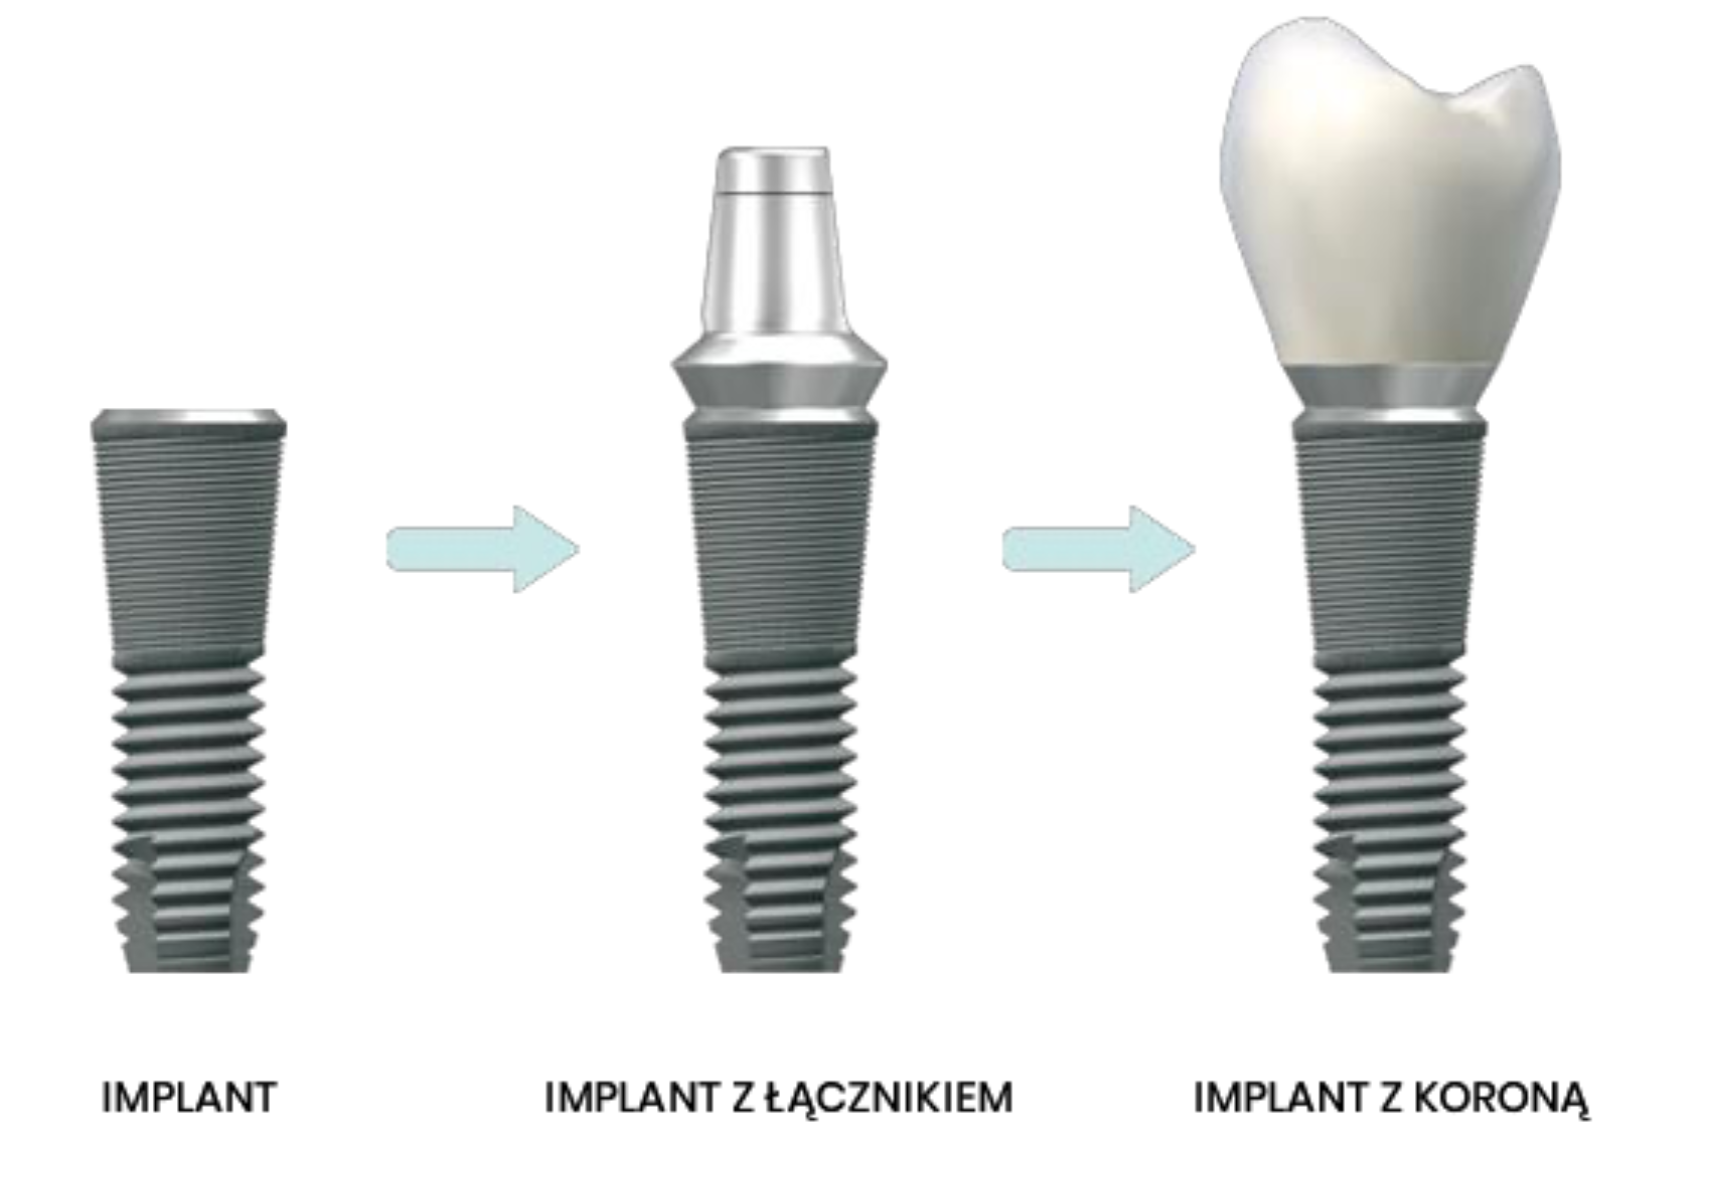

Sam implant na tym etapie nie uzupełnia braku w uzębieniu. Pełna funkcjonalność zapewniona jest dopiero po zamocowaniu w implancie korony, mostu lub protezy. W części protetycznej uzupełniania uśmiechu – wykonywanej po pełnym procesie osteointegracji – możliwe jest założenie nowego zęba lub zębów.